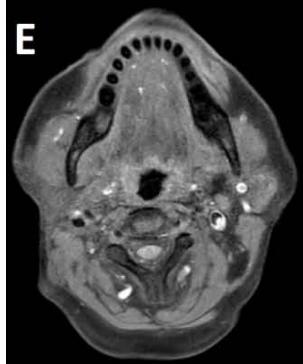

Figure/Patient 6

Another case of a right latero-cervical lymphangioma in a 8 year-old boy, markedly hyper-intense on T2 axial (A) and coronal scans (B) and slightly hyper-intense on T1 axial (C) and coronal (D) MR scans. The patient is demanded for sclerotherapy with ethanol: no recurrence is visible at the follow-up MR T2 (E-F) and T1 scans (G-H).